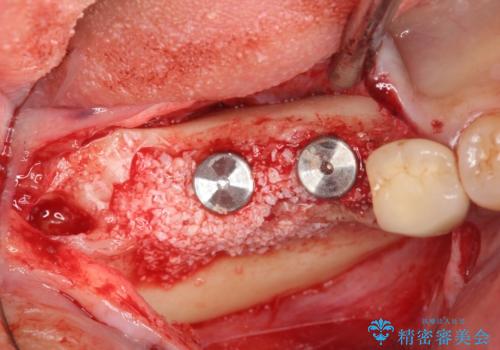

インプラントの埋入には十分な骨量が必要ですが、虫食い状に骨が足りなかった為インプラントの埋入と同時に骨の増成を行いました。

インプラントを埋入する手術と同時に骨の増成を行う場合と、埋入前に骨の造成だけを行う場合があります。